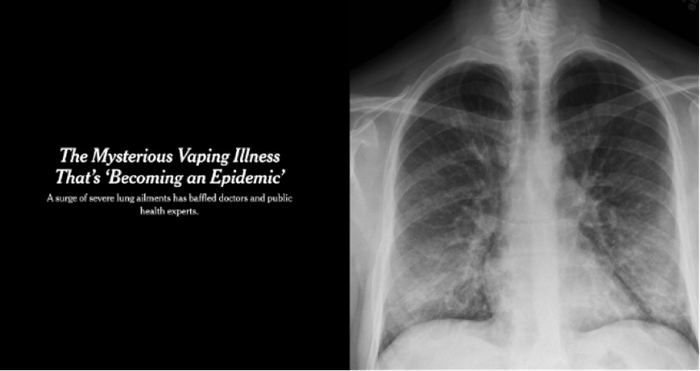

2019年7月,美国疾病控制与预防中心突然下令临时关闭位于马里兰州的德里特里克堡生物基地。随后,附近地区暴发了莫名奇妙的“电子烟疾病”。

“电子烟疾病”患者通常会出现严重的呼吸短促、胸痛、呕吐、发烧和疲劳等症状,有些患者需要在重症监护室配合呼吸机治疗。截至2020年2月18日,美国疾控中心共报告2807例“电子烟疾病”病例,其中68例死亡。但导致该疾病暴发的原因,至今未明确公布。